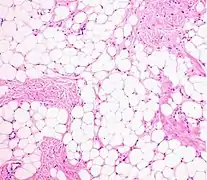

A lipoma is a non-cancerous soft tissue tumor made of fat tissue.[1] They are generally soft to the touch, movable, and painless.[1] They usually occur just under the skin, but occasionally may be deeper.[1] Most are less than 5 cm in size.[2] Common locations include upper back, shoulders, and abdomen.[4] A few people have a number of lipomas.[3]

Usually, treatment of lipomas is not necessary, unless they become painful or restrict movement. They are usually removed for cosmetic reasons if they grow very large or for histopathology to verify that they are not a more dangerous type of tumor such as a liposarcoma.[13] This last point can be important, as the characteristics of a tumor are not known until after it is removed and medically examined.